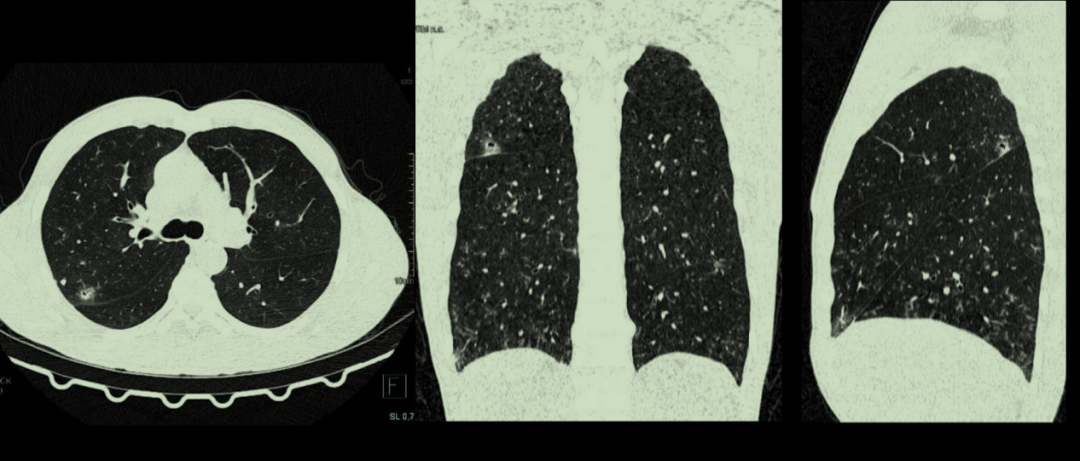

西门子SOMATOM go.Top 64排CT还具有扫描速度快、辐射剂量小、空间分辨率高、精准成像、AI处理系统功能齐全等特点。除了常规CT检查、普通增强CT检查外,还可对全身大血管、脑血管、心脏血管进行检查,可实现胸部、腹部、下肢血管的联合扫描,在清楚显示的前提下大大降低了被检查者的辐射。

肺低剂量筛查